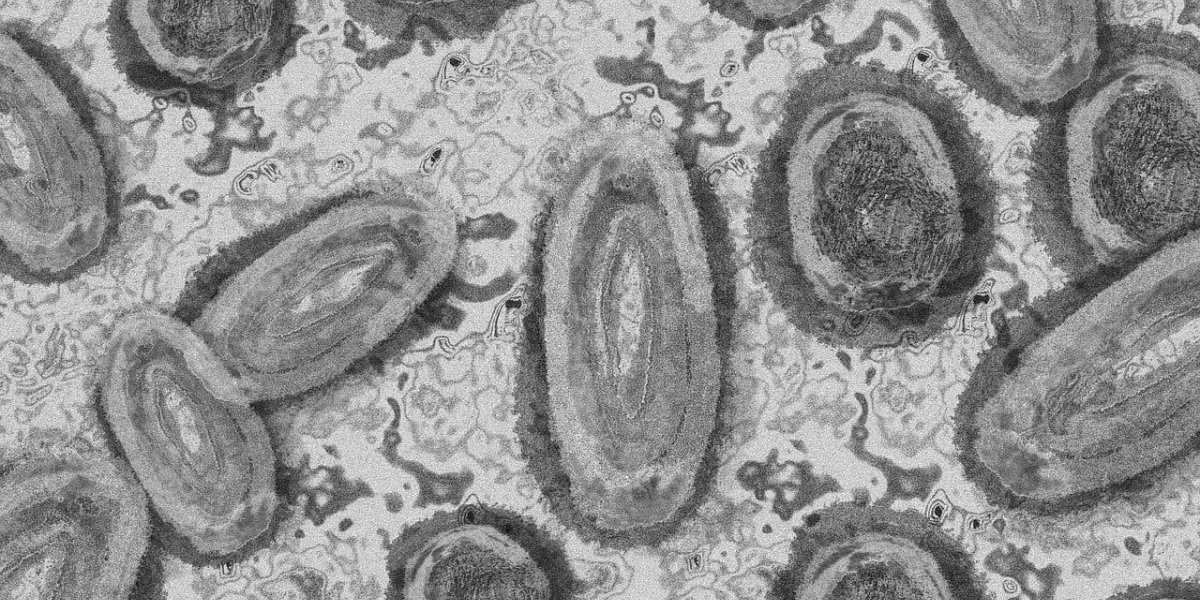

Confirmado primeiro caso de varíola dos macacos no Brasil

Nesta quarta-feira (8), o primeiro caso de varíola dos macacos no Brasil foi confirmado na cidade de São Paulo. Um homem de 41 anos que viajou à Espanha é o infectado. Ele está em isolamento no Hospital Emílio Ribas, na zona oeste da capital.